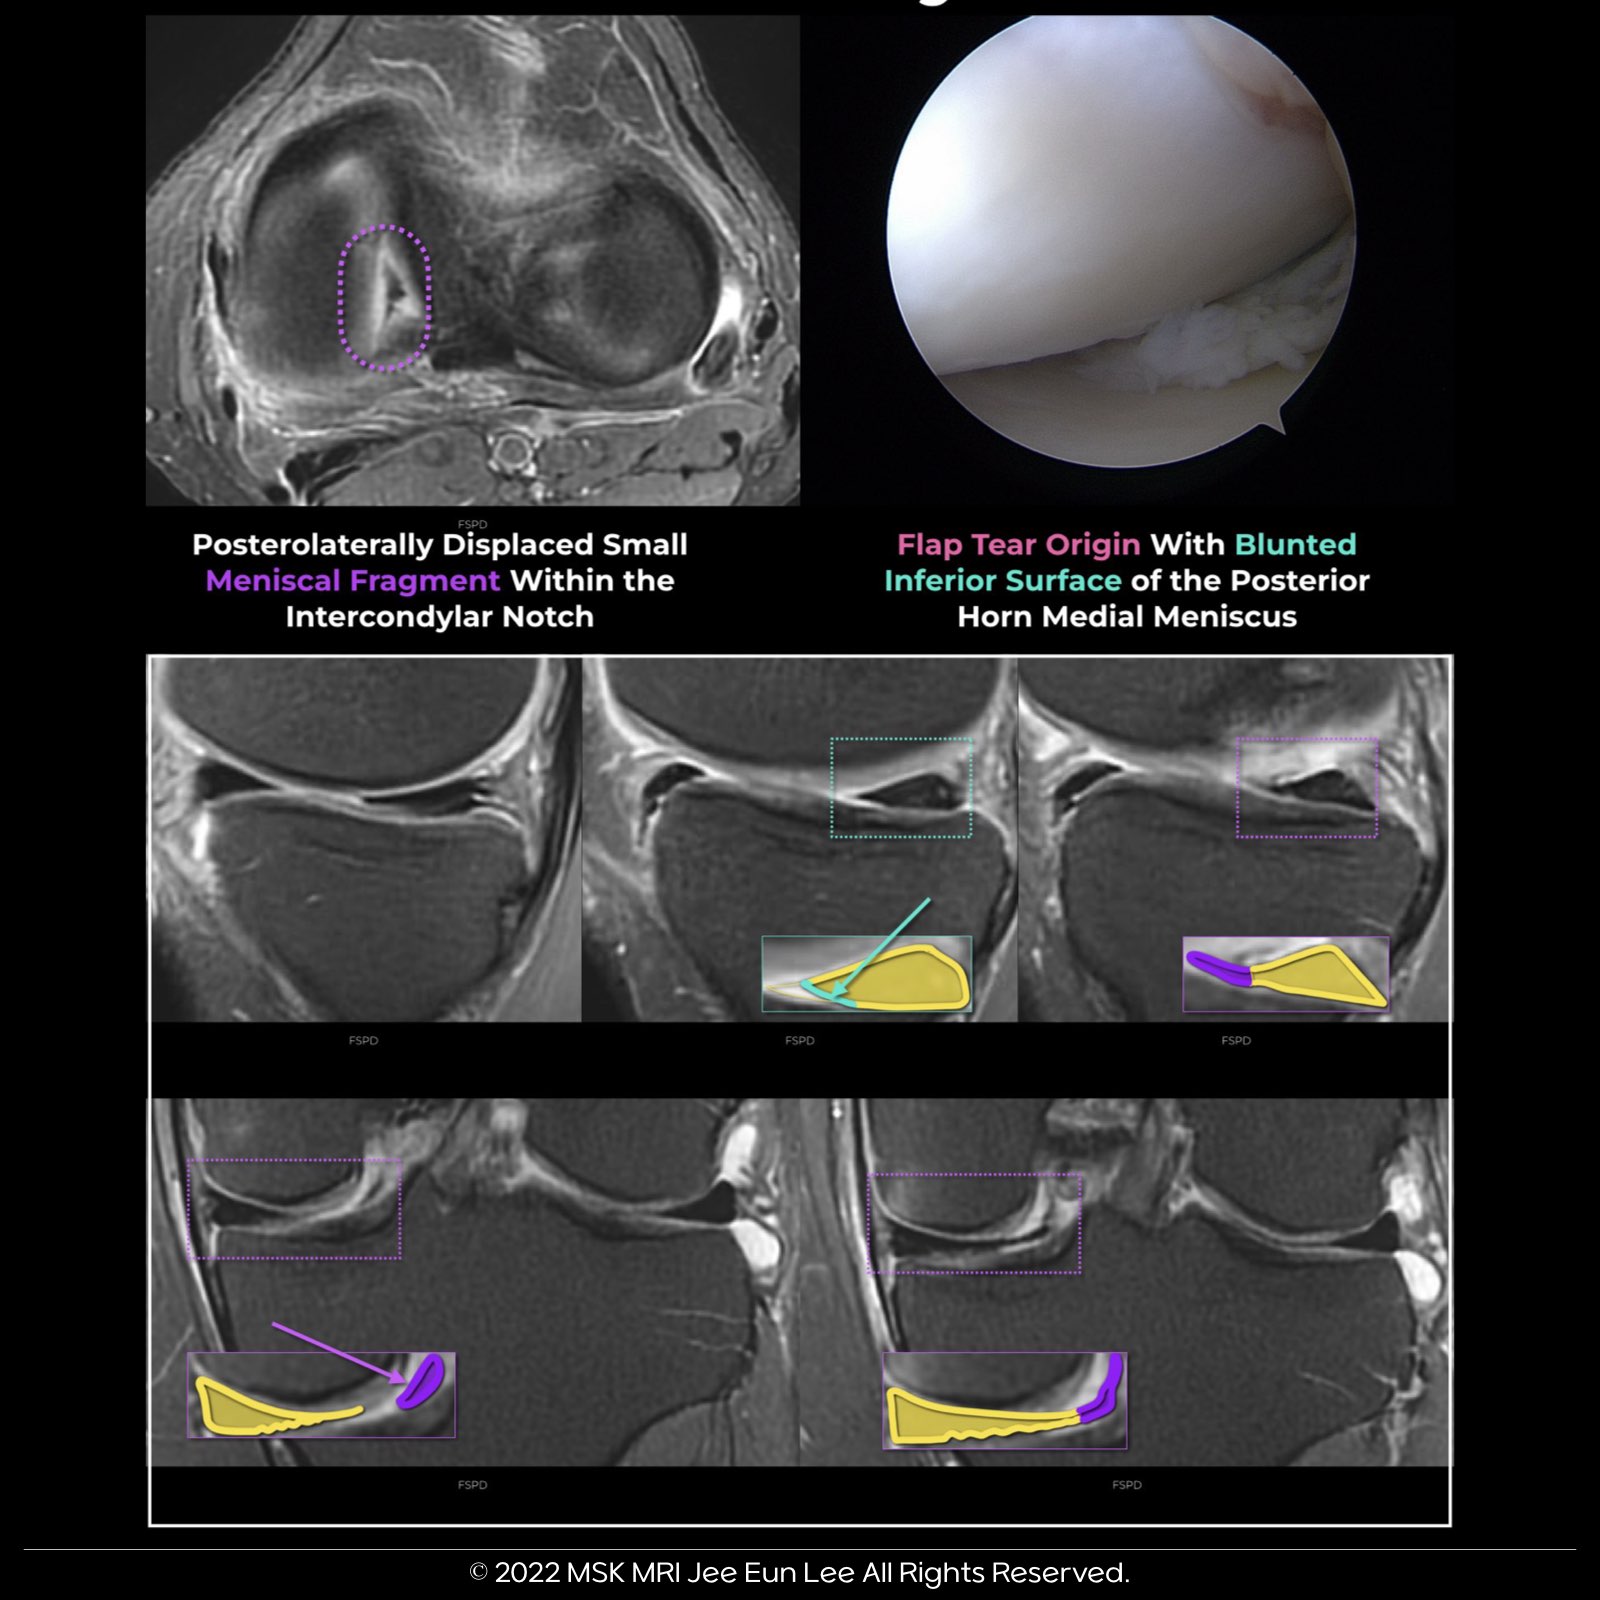

1️⃣ Bucket-Handle Tear with Displacement

2️⃣ Flap Tear with Displacement

3️⃣ Free Fragment Displacement

Identifying any displaced fragments is crucial.

Why? Because they can be easily missed during surgery, leading to less-than-optimal outcomes.

Unlike stable horizontal cleavage tears, unstable meniscal tears pose a greater risk of damaging the hyaline cartilage.